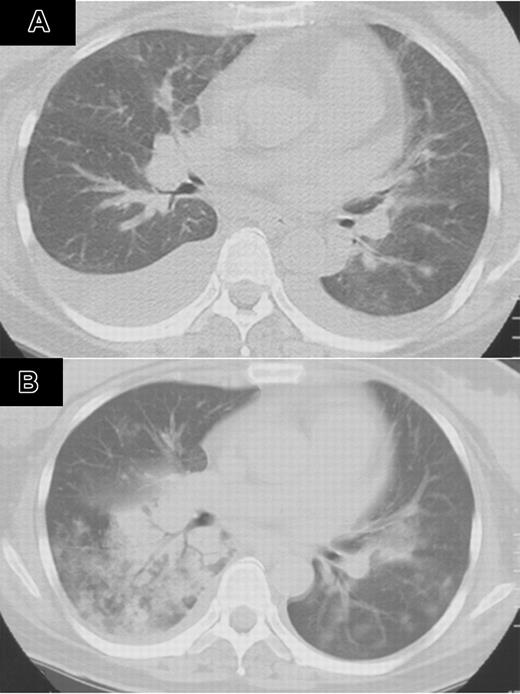

A 47-year-old woman with multiple myeloma, immunoglobulin G (IgG) type, underwent autologous peripheral blood stem cell transplantation (auto-PBSCT) following 200 mg/m2 melphalan. She had no history of smoking. She had a history of invasive pulmonary aspergillosis, which was successfully treated with antifungal agents. Three months after auto-PBSCT, her disease recurred. She had no signs of infection, and her performance status (PS) was 1.7 Bortezomib (1.3 mg/m2) twice a week was given for 2 weeks. Cough and dyspnea developed 8 days after completion of bortezomib. Oxygen saturation dropped to 87%, and chest computed tomography (CT) revealed bilateral pleural effusions (Figure 1A). Peripheral leukocyte count was 5.6 × 109/L. Oxygen and diuretics did not improve her condition. After 40 mg dexamethasone for 4 days, her respiratory symptoms disappeared. The second course of bortezomib was started at the same dose on day 23 of the first course. On day 12 of the second course, she developed recurrent cough, asthmalike symptoms, fever, and dyspnea. Chest CT showed bilateral infiltrates, which rapidly spread to the entire lung fields (Figure 1B). Infection was not identified with sputum cultures. She received granulocyte colony-stimulating factor (G-CSF), beta-lactams, carbapenems, flulconazole, itraconazole, acyclovir, and amphotericin B. Although her respiratory symptoms temporarily improved with 125 to 1000 mg methylprednisolone for 3 days, she died of respiratory failure. Autopsy showed diffuse hyaline membranous changes with partial organization in alveolar cavity and its airway. Pathologic diagnosis was consistent with acute and organizing diffuse alveolar damage.

Computed tomography of the chest after treatment with bortezumib (patient 1). (A) CT of the chest 8 days after completion of bortezomib showed bilateral pleural effusion. (B) CT of the chest on day 12 of the second course of bortezomib showed bilateral infiltrates, which rapidly spread to the entire lung field.